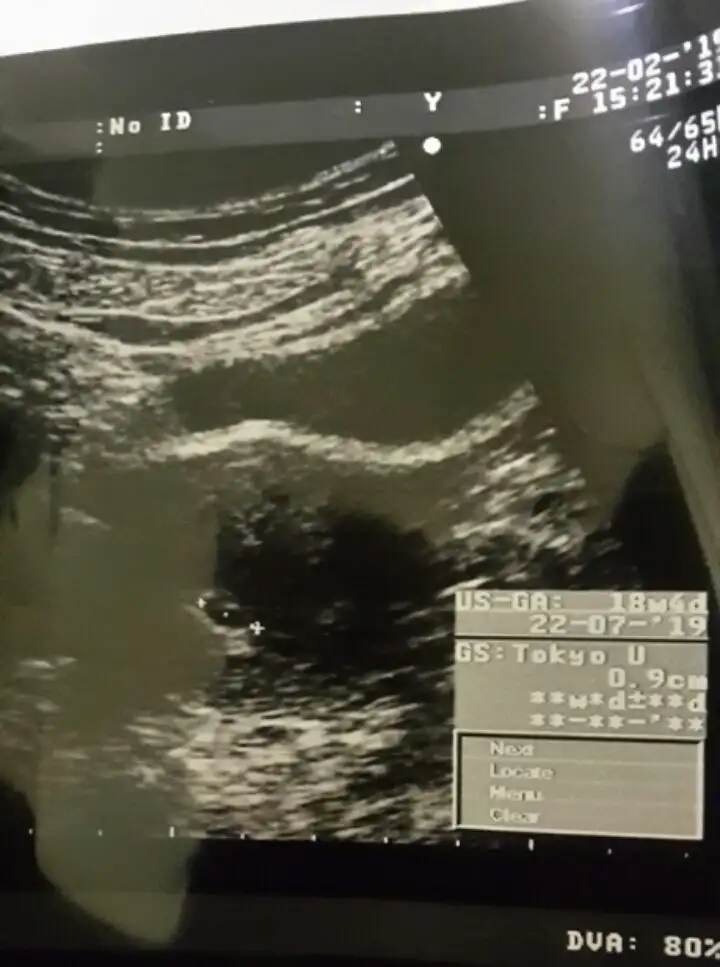

Günaydın kızlar ultrason fotoğrafını yüklemistim daha önce aklıma takılan kağıdın yanında 18 hafta 4 gün yazıyo tarihte 7. Ay makinenin ayarlarından olabilirmi bugün sifirlandim 5+0 oldu

• 2019-02-23 21.56.37.webp

25,5 KB · Görüntüleme: 70

Ona takılma canım yanlış bi tarih belli ki. Senden önce muayene olan birinin bilgileri kalmış olabilir. Ama senin keseni ölçerken senin tarihini ve haftanı hesaplamalıydı doktor